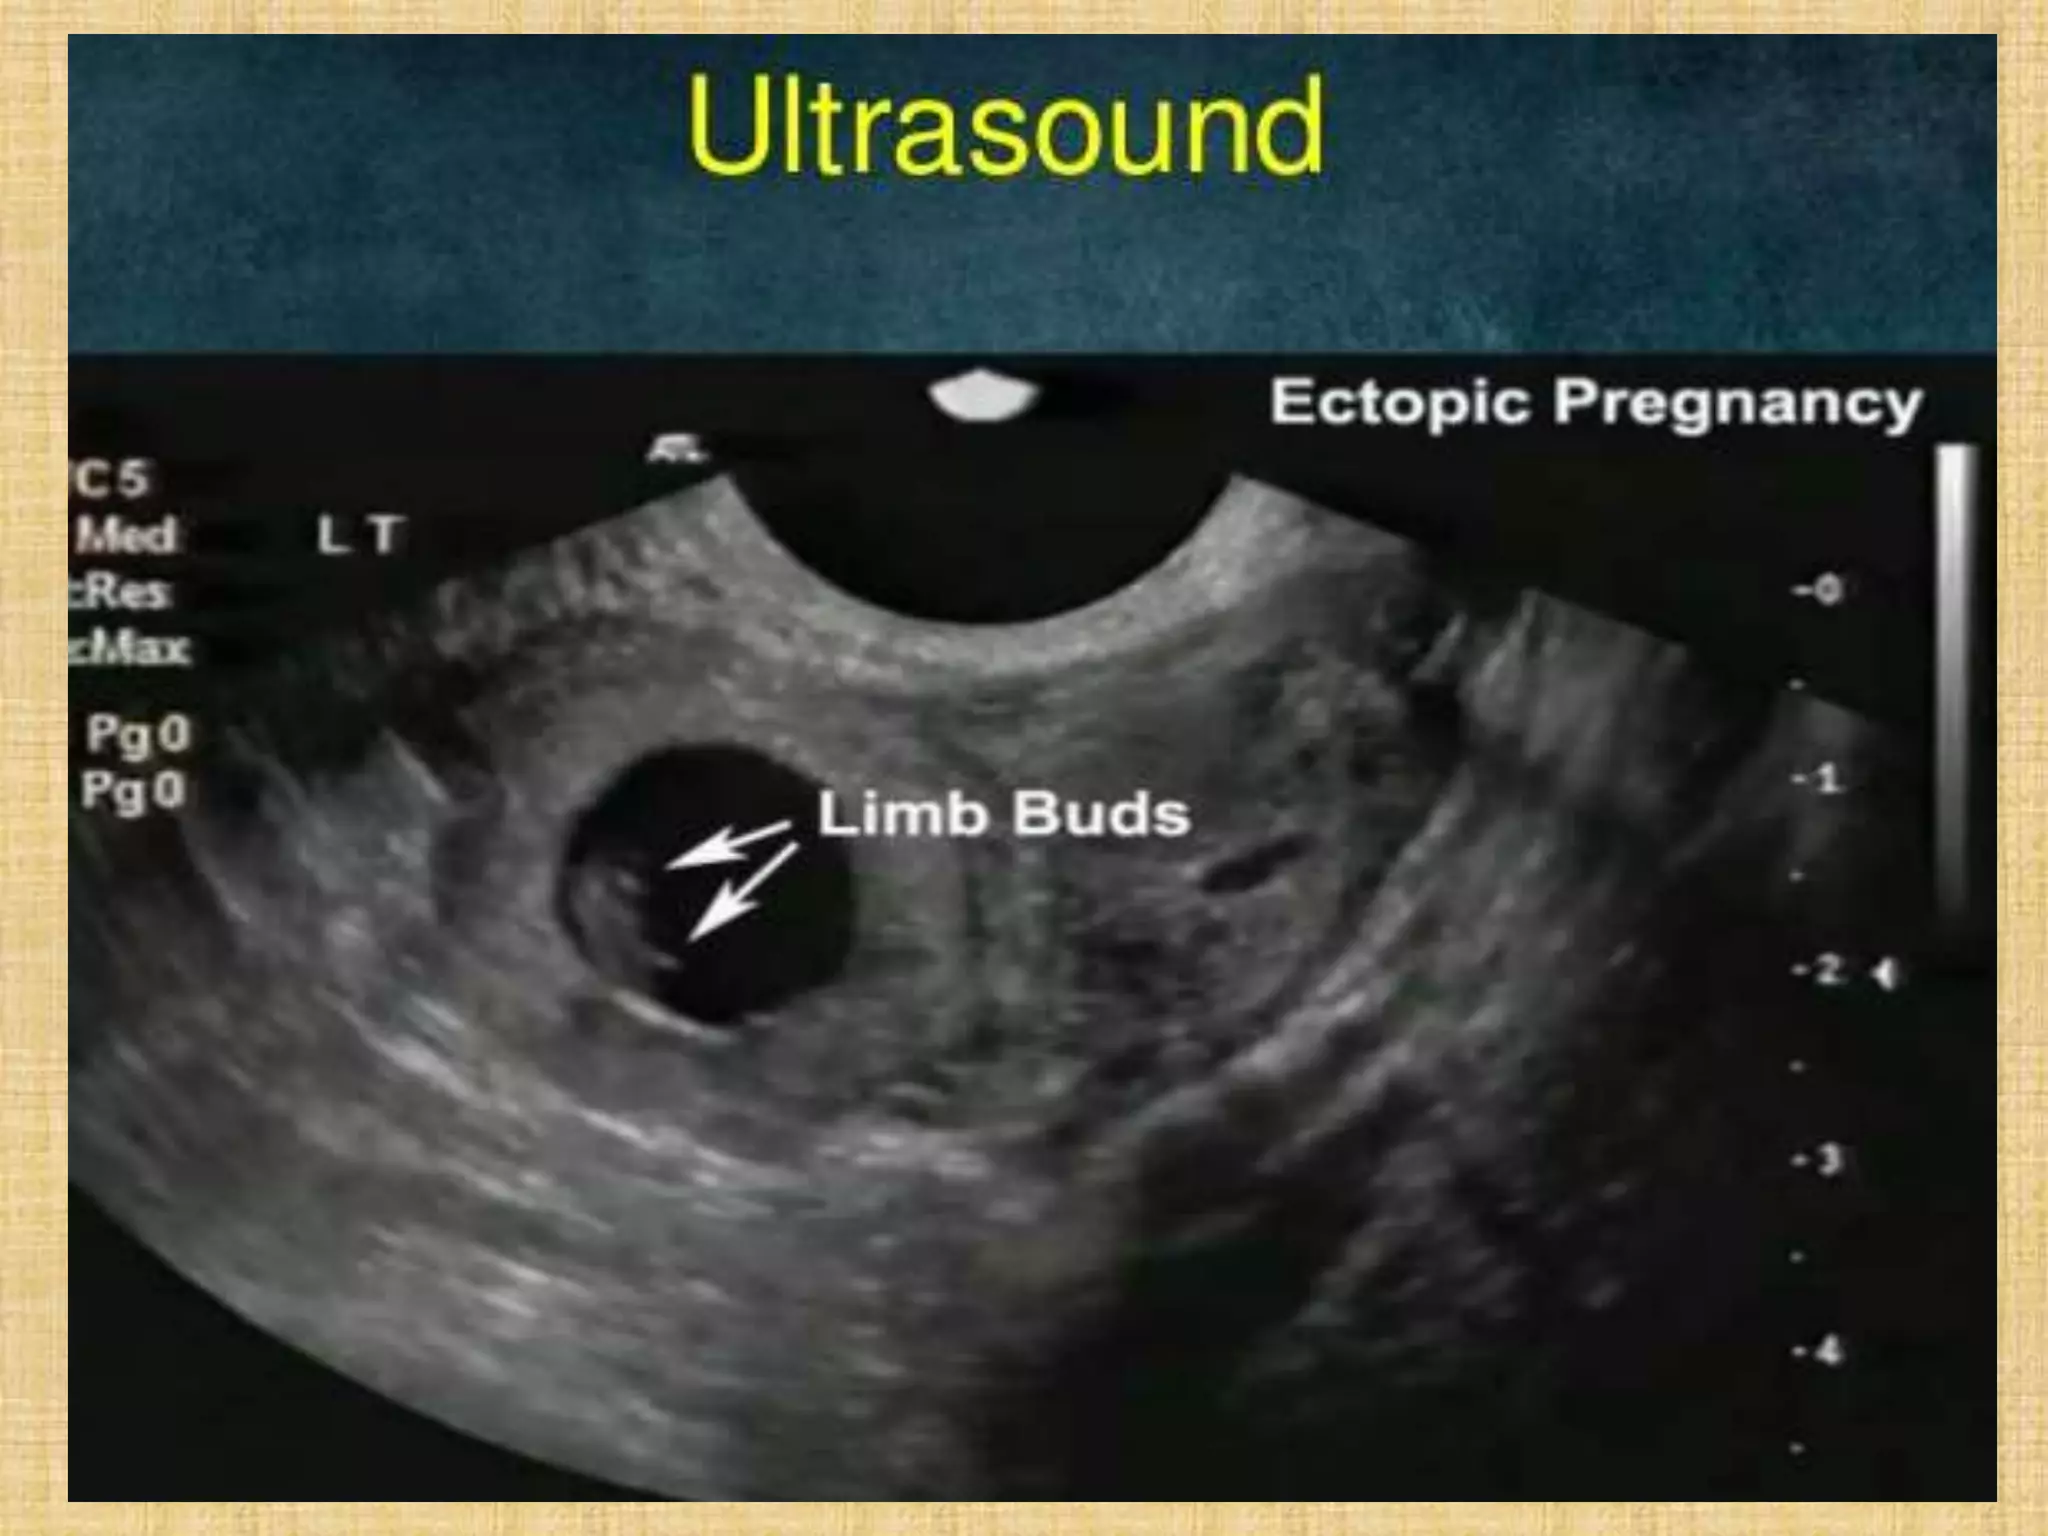

Tubal pregnancy in a 41-

year-old woman with acute

abdominal pain and

positive results of a

pregnancy test.

Tubal pregnancy ina 41- year-old woman with acute abdominal pain and positive results of a pregnancy test.